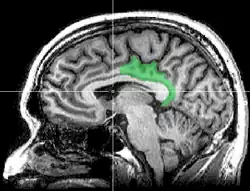

Sagittal MRI slice with highlighting indicating location of the posterior cingulate

The posterior cingulate cortex (PCC) is the caudal part of the cingulate cortex, located posterior to the anterior cingulate cortex. This is the upper part of the "limbic lobe". The cingulate cortex is made up of an area around the midline of the brain. Surrounding areas include the retrosplenial cortex and the precuneus.